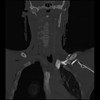

23 ANGIO,CE,Cor-MIP,5.000,ANGIO,Cor-MIP,